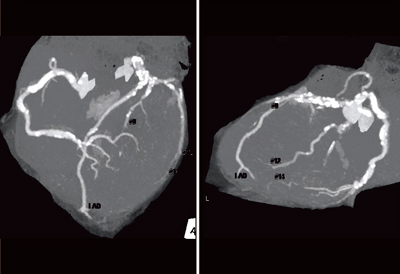

冠動脈の石灰化が非常に強く,冠動脈CTでの評価は容易ではない(図4)。curved MPR画像にて,LCX #13に強い狭窄があることは確認できたものの,RCAステント留置部やLAD,対角枝については,はっきりと評価できない(図5)。

![]() 図4 症例2:冠動脈CT |

![]() 図5 症例2:curved MPR画像 |